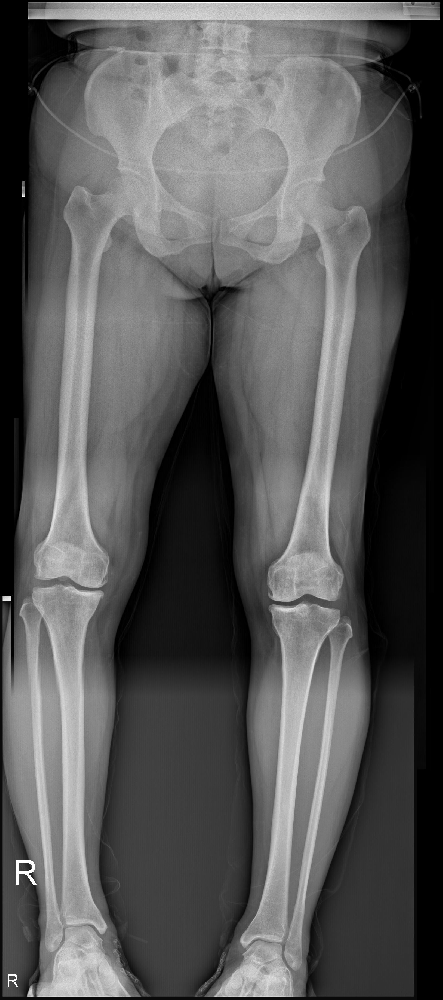

李煥云,51歲的女性,來自市中區(qū)永安鄉(xiāng)天西村。她帶著7年疼痛的右膝和2年疼痛的左膝走入市中區(qū)誠德骨科醫(yī)院。歲月的磨礪使她變得堅(jiān)強(qiáng),而疼痛卻成了她生活的沉重負(fù)擔(dān)。讓我們跟隨她的腳步,一同探索她心中的堅(jiān)韌和勇氣。

病情的加重使她決定前往市中區(qū)誠德骨科醫(yī)住院接受更全面的檢查。在這次住院期間,醫(yī)生進(jìn)行了雙側(cè)脛骨高位截骨加接骨板螺釘內(nèi)固定手術(shù),而術(shù)后的康復(fù)進(jìn)展令人欣喜。

圖片1.png